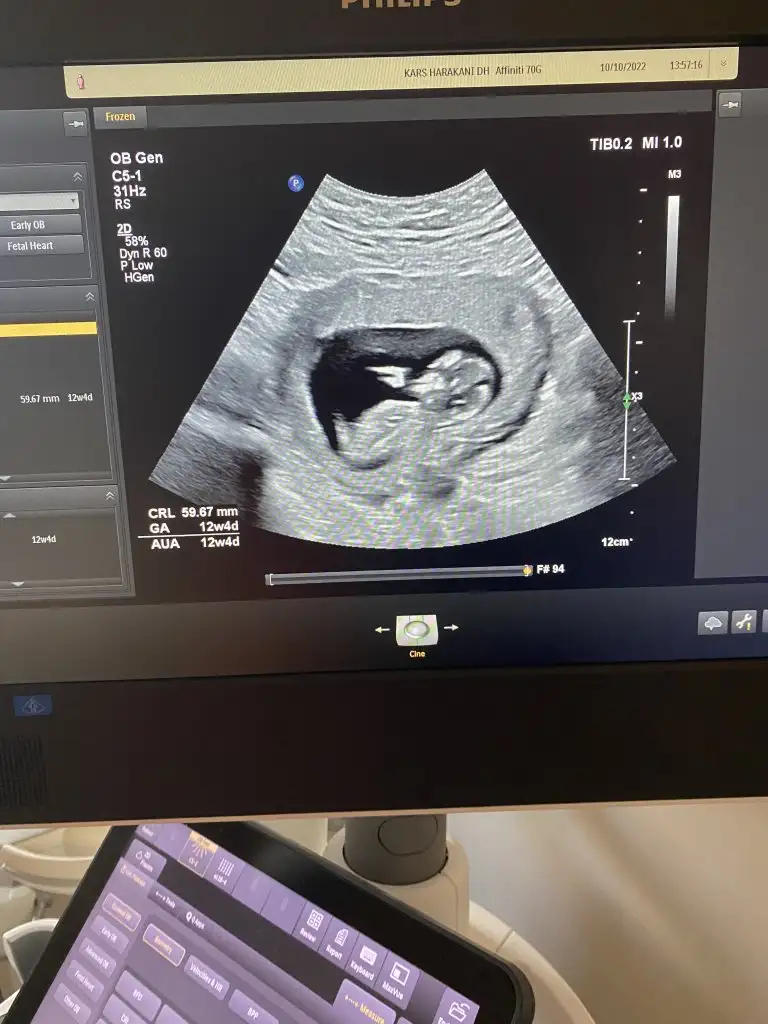

kızlar burd 12 haftalıgım fotoya gore kız mı erkek mı bu nub teorisinden anlamıyorum ben

• 5529A175-83A2-4C6A-A943-0487AB0731D9.webp

5529A175-83A2-4C6A-A943-0487AB0731D9.webp

31,2 KB · Görüntüleme: 68